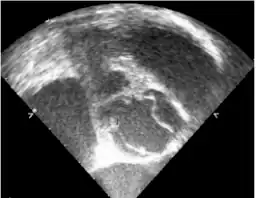

-

Transesophageal echocardiography- the right side commissure of the bicuspid aortic valve is ruptured -